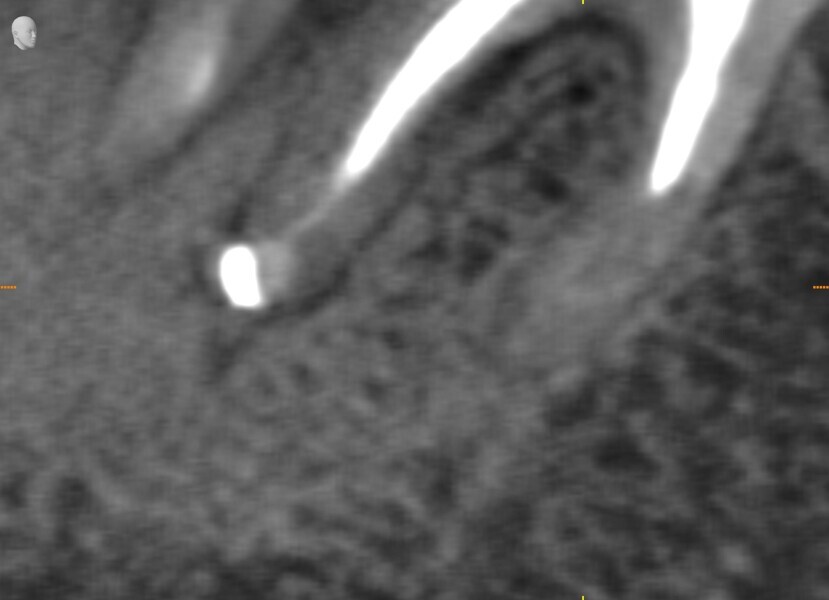

During the consultation appointment, a CBCT scan was performed. It revealed a small osteolytic lesion around the mesial root, suggesting the possibility of achieving patency in the root canals in the mesial root. Around the distal root, there were no signs of the lesion, which indicated that the mesial root was the cause of the symptoms. The radiographic examination also revealed a broken lentulo in the MB canal (Fig. 16).

Figs. 16 a & b